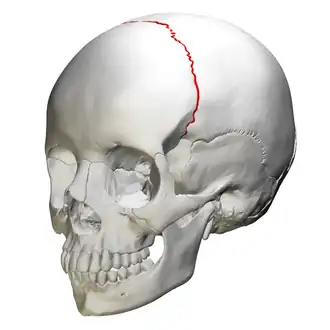

![]() Anterolateral view of coronal suture (red) | |

Animation. Coronal suture shown in red. -